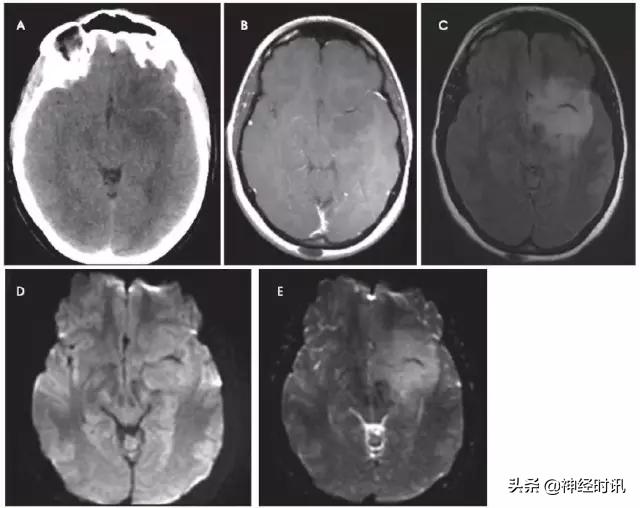

脑肿瘤

原发性脑肿瘤可以表现为急性神经功能缺损。有时低级别胶质瘤伴轻度水肿效应和皮层受累可能会与亚急性脑梗死混淆(图3),通过无血管分布、无明显弥散受限和脑沟强化,较易与其鉴别。但是,亚急性梗死伴出血和高级别出血性胶质瘤可表现为局部弥散受限、不同程度强化和占位效应,有时难以鉴别。

图3 一例49岁女性,突然醒来出现言语不清。最初CT报告左侧MCA区域脑梗死伴左侧MCA高密度(A),MRI显示非强化(B)、T2-FLAIR高信号(C)的膨胀性病灶伴弥散增加(D-DWI,E-ADC)。活检显示为间变性少突胶质细胞瘤。